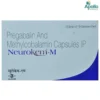

Product introduction

Neurotab-NT Tablet is taken by mouth, with or without food, and preferably at night. It is advised to take it at a fixed time each day to maintain a consistent level of medicine in the blood. In case you miss a dose of this medicine, take it as soon as you remember. Finish the full course of treatment even if you feel better. It is important not to stop taking this medicine suddenly without talking to the doctor, as it may worsen your symptoms.